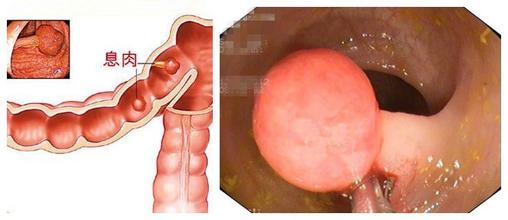

导语 肠息肉是肠道内的病变,它可小至芝麻、绿豆,也可大至核桃大

导读 肠子上长息肉这一病症在医学上称之为肠息肉。肠息肉是一种良性的病变

导语 肠息肉泛指肠道粘膜表面向肠腔突出的隆起性病变从病理上来看,其内容 查看更多